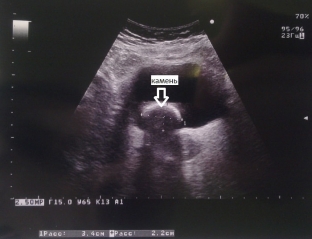

Одним із найбільш інформативних методів діагностики сечокам'яної хвороби є ультразвукове дослідження. Ультразвукове дослідження дозволяє визначити характерні акустичні ознаки каменів ниркових чашок і балій: конкременти дають сильний ехо-сигнал, за каменем утворюється акустична циліндрична або конічна тінь, інтенсивність якої залежить від складу і розмірів каменю. Коралоподібні камені при ультразвуковому дослідженні мають вигляд ехогенної структури, яка повторює форму чашечно-баханкової системи, повністю або частково заповнюючи її. Важливо враховувати той факт, що ультразвукове дослідження дозволяє побачити каміння, розмір якого більше 3 мм.